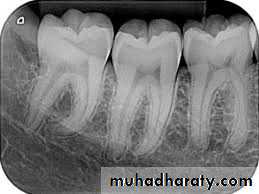

A. Intra oral (periapical, bitewing, occlusal)